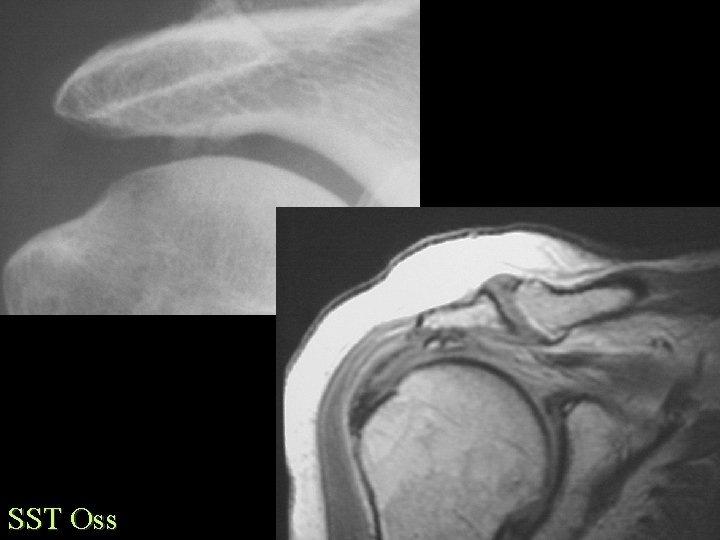

Ossification Traumatic Tendons and Ligaments • Calcification common, Ossification rare • • • MCL knee - Pellegrini-Stieda Coracoclavicular Achilles tendon Supraspinatus Stylohyoid ligament XS - Eagle syn.

SST Oss